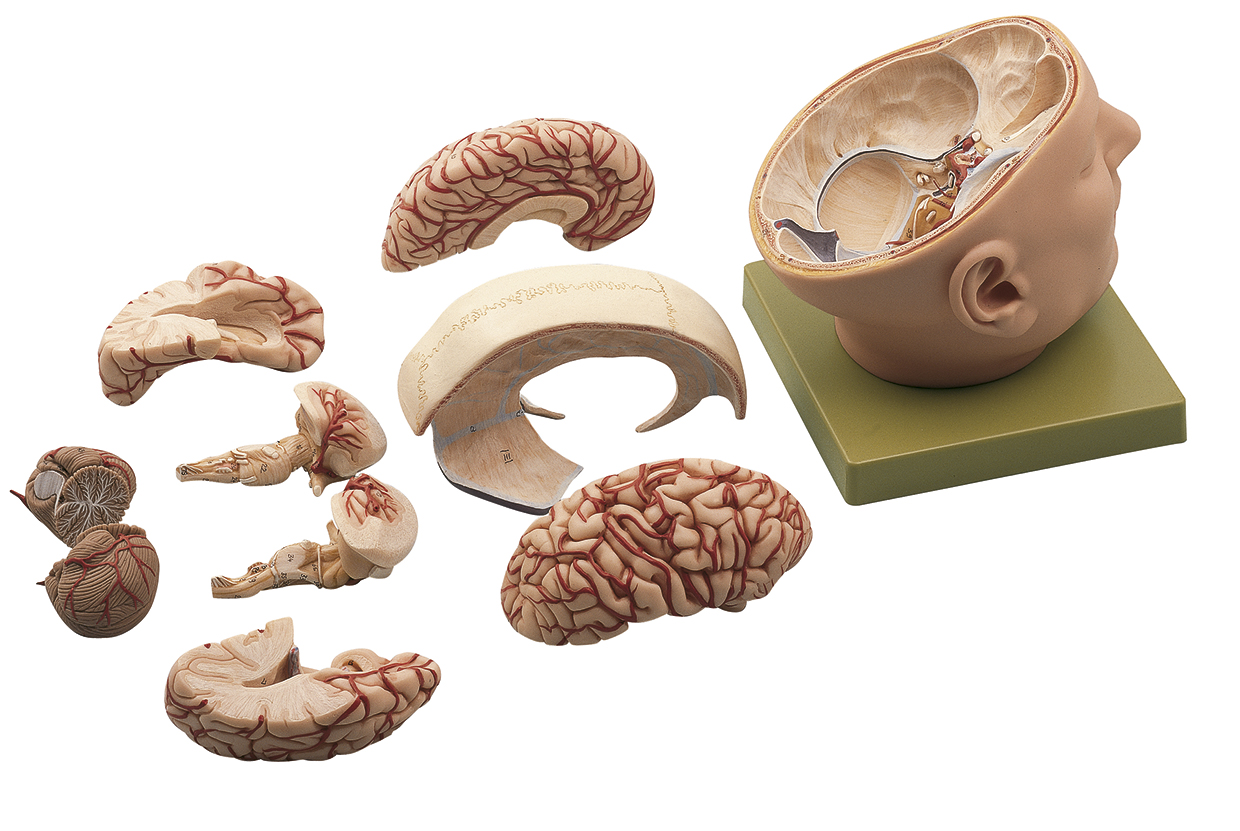

Base of the Head (BS 5/1) · Anatomy models | SOMSO®,

Base of the Head (BS 5/1) · Anatomy models | SOMSO®, SOMSO Situs of the Base of the Skull – GTSimulators.com,

SOMSO Situs of the Base of the Skull – GTSimulators.com, SOMSO Median Section of the Head – GTSimulators.com,

SOMSO Median Section of the Head – GTSimulators.com, Somso Median Section of the Head, Anatomical Model,

Somso Median Section of the Head, Anatomical Model, SOMSO 14-Piece Model of the Human Skull – GTSimulators.com大脳鎌付きの頭部模型です。写真のように細かなパーツにまで分解できます。リアリティのあるものが欲しい方は是非。ちなみに、ヒト頭部骨標本(本物: 下顎、歯牙も全て揃っています)もあります。欲しい方はコメントください。本物で頭蓋底などを勉強したい人にお譲りします。(価格は安くはありませんが、、)

SOMSO 14-Piece Model of the Human Skull – GTSimulators.com大脳鎌付きの頭部模型です。写真のように細かなパーツにまで分解できます。リアリティのあるものが欲しい方は是非。ちなみに、ヒト頭部骨標本(本物: 下顎、歯牙も全て揃っています)もあります。欲しい方はコメントください。本物で頭蓋底などを勉強したい人にお譲りします。(価格は安くはありませんが、、)